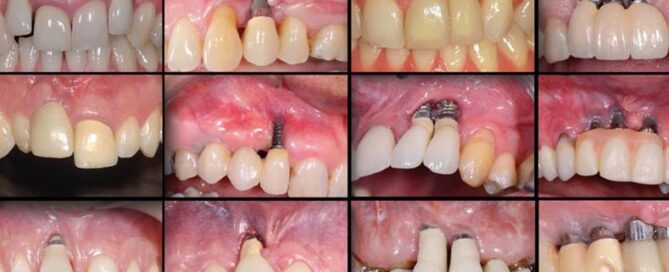

Se você está aqui porque notou que seu implante dental [...]

Muitos pacientes sonham em voltar a sorrir com confiança, mas [...]